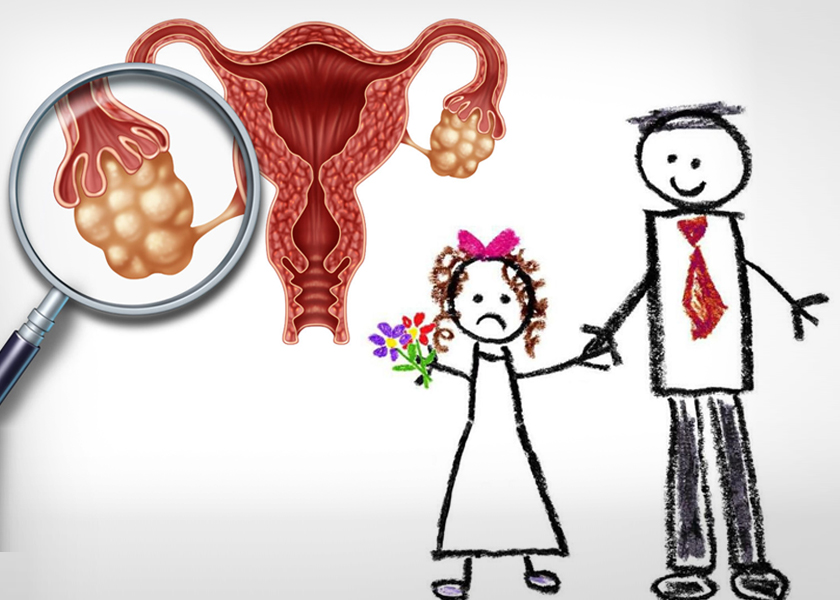

পলিসিস্টিক ওভারি সিনড্রম হলে তাড়াতাড়ি বিয়ে নয়!

বহু তরুণীর অভিভাবকদের একটি ভ্রান্ত ধারণা থাকে যে বিয়ের পর পলিসিস্টিক ওভারি সিনড্রমের সমস্যা কেটে যাবে। আরও স্পষ্ট কথায় বললে, অনেকেই ভাবেন মেয়ে বাচ্চার জন্ম দিয়ে দিলে পলিসিস্টিকের জন্য আর কোনো টেনশন থাকবে না।

লাইফস্টাইল ও পরিবেশের পরিবর্তনের জন্য শহরের কিশোরী, তরুণীদের মধ্যে এই সিনড্রমে আক্রান্ত হওয়ার সংখ্যা হুহু করে বাড়ছে ঠিকই। তা বলে মেয়ের তাড়াতাড়ি বিয়ে দিলে পিসিওএস প্রতিরোধ করা যাবে এমন ধারণা সম্পূর্ণ ভুল। যুগ বদলেছে। আধুনিক চিকিৎসাবিজ্ঞানের কল্যাণে অহেতুক ভয় পাওয়ার কিছু নেই। পলিসিস্টিক ওভারির চিকিৎসায় আমূল পরিবর্তন হয়েছে। পলিসিস্টিকের জন্য তাড়াতাড়ি বিয়ে করে গর্ভধারণ করার দরকার নেই। তবে ৩০ বছরের মধ্যে মা হয়ে যাওয়াই ভালো। তা না হলে অন্যান্য জটিলতা হতে পারে।

শরীরে হরমোনের ভারসাম্য বিঘ্নিত হলে পলিসিস্টিক ওভারি সিনড্রম হয়। অনিয়মিত ঋতুস্রাব হলে ডিম্বাণু নিঃসরণ ঠিকমতো হয় না। এটা এমন কিছু সমস্যার বিষয় নয়। তা ছাড়া, পলিসিস্টিক ওভারি হলেই যে অপারেশন করতে হবে- এমন কোনো দরকার নেই।